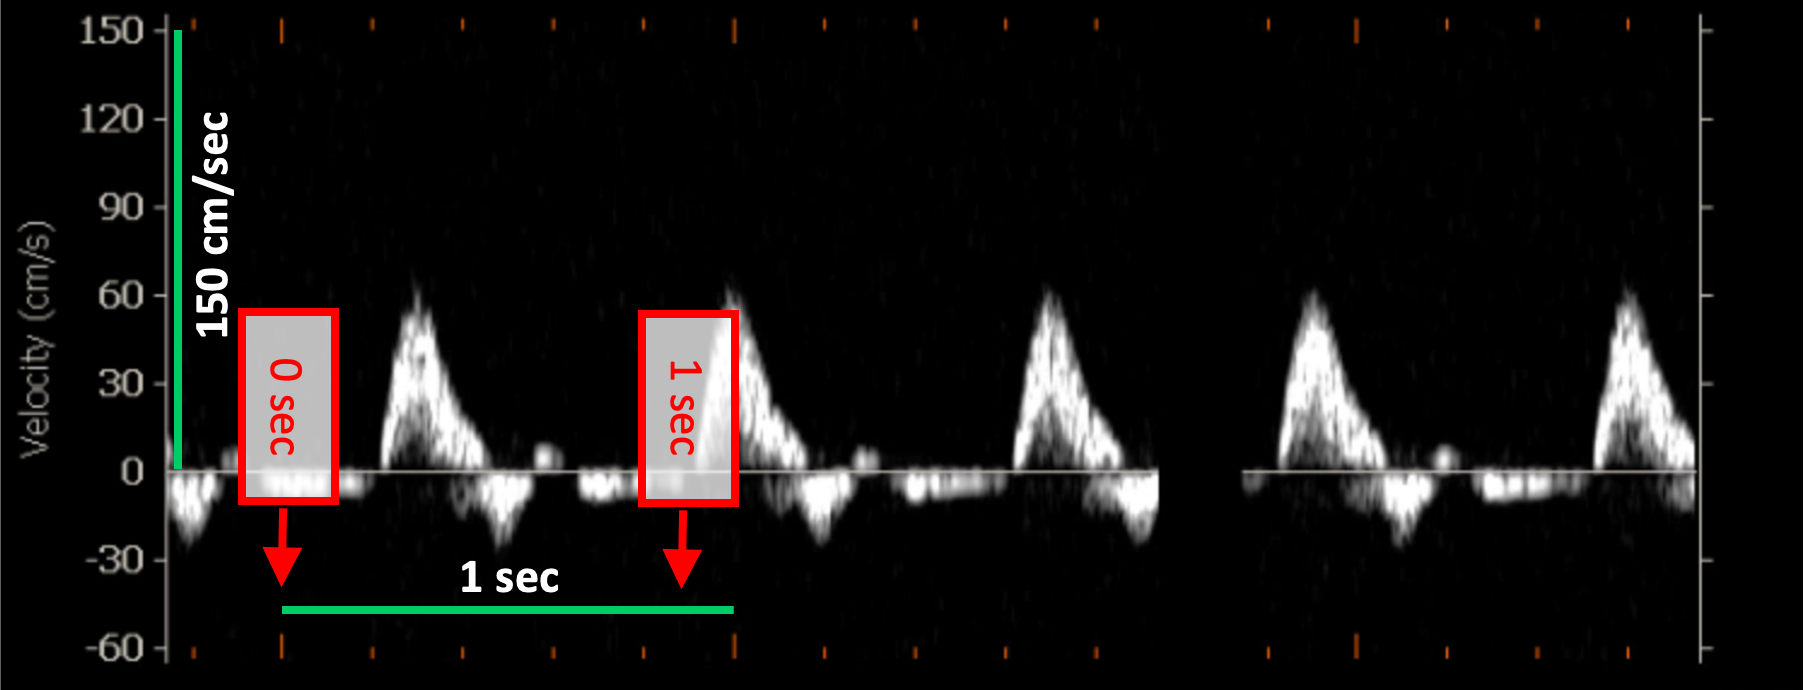

Doppler velocity calibration examples

The following images show examples of calibrations of the Doppler velocity image. Graphic items in red shows where you can find the information about the time scale in the ultrasound image.